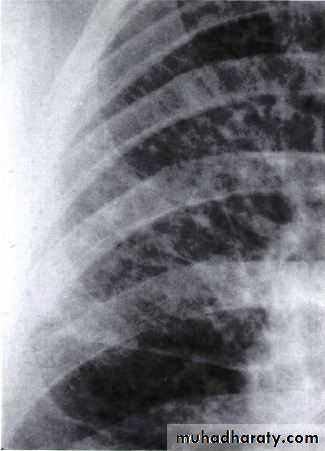

lymphangitis carcinomatosa• These lines represent lymphatics infiltrated by tumour.

LUNG CANCER - Dr. Mustafa Nema- Baghdad College of MedicineRadiology

The most frequent finding is a mass in the lung field.Secondary manifestations seen on the CXR include lobar collapse, total lung collapse, pneumonitis because of endobronchial obstruction, elevation of the hemidiaphragm,

Elevation of the hemidiaphragm

lobar collapse & pneumonitis